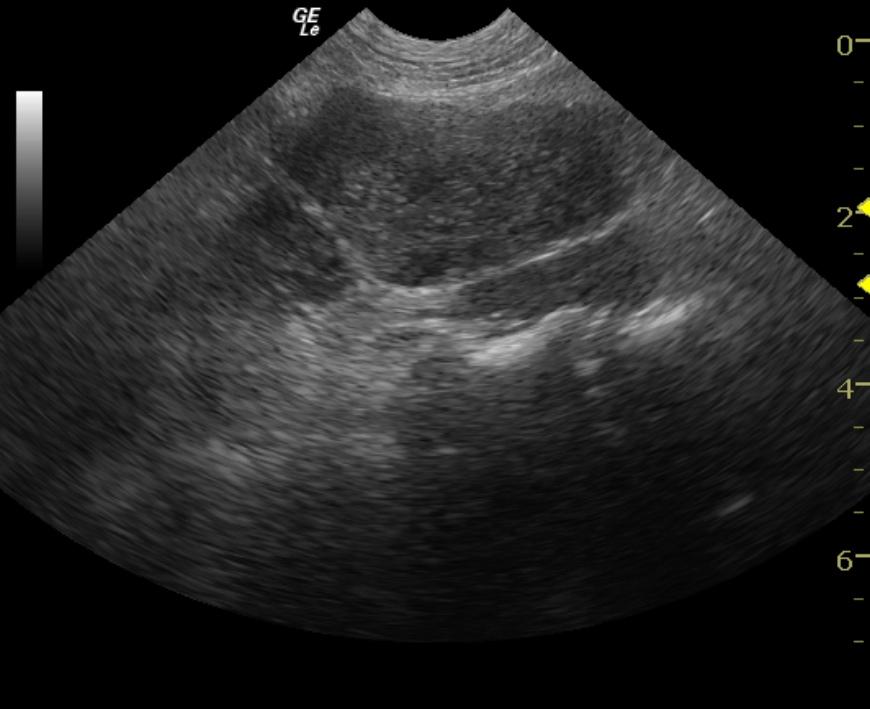

An 11-year-old FS Jack Russell Terrier dog with history of MCT – grade II on the foot in 1999 and grade I on the skin in 2004, was presented for pruritus near the base of tail. The only significant finding on physical examination was a 1.5 cm ulcerated mass in the right ventral anal mucosa. Eosinopenia and elevated MCV and MCHC were evident on CBC. The mass was surgical excised and the patient treated with antibiotics. Biopsy results showed a grade II MCT. The patient was presented three months later for recurrence of the anal mass. Abdominal ultrasound was advised prior to further surgery.